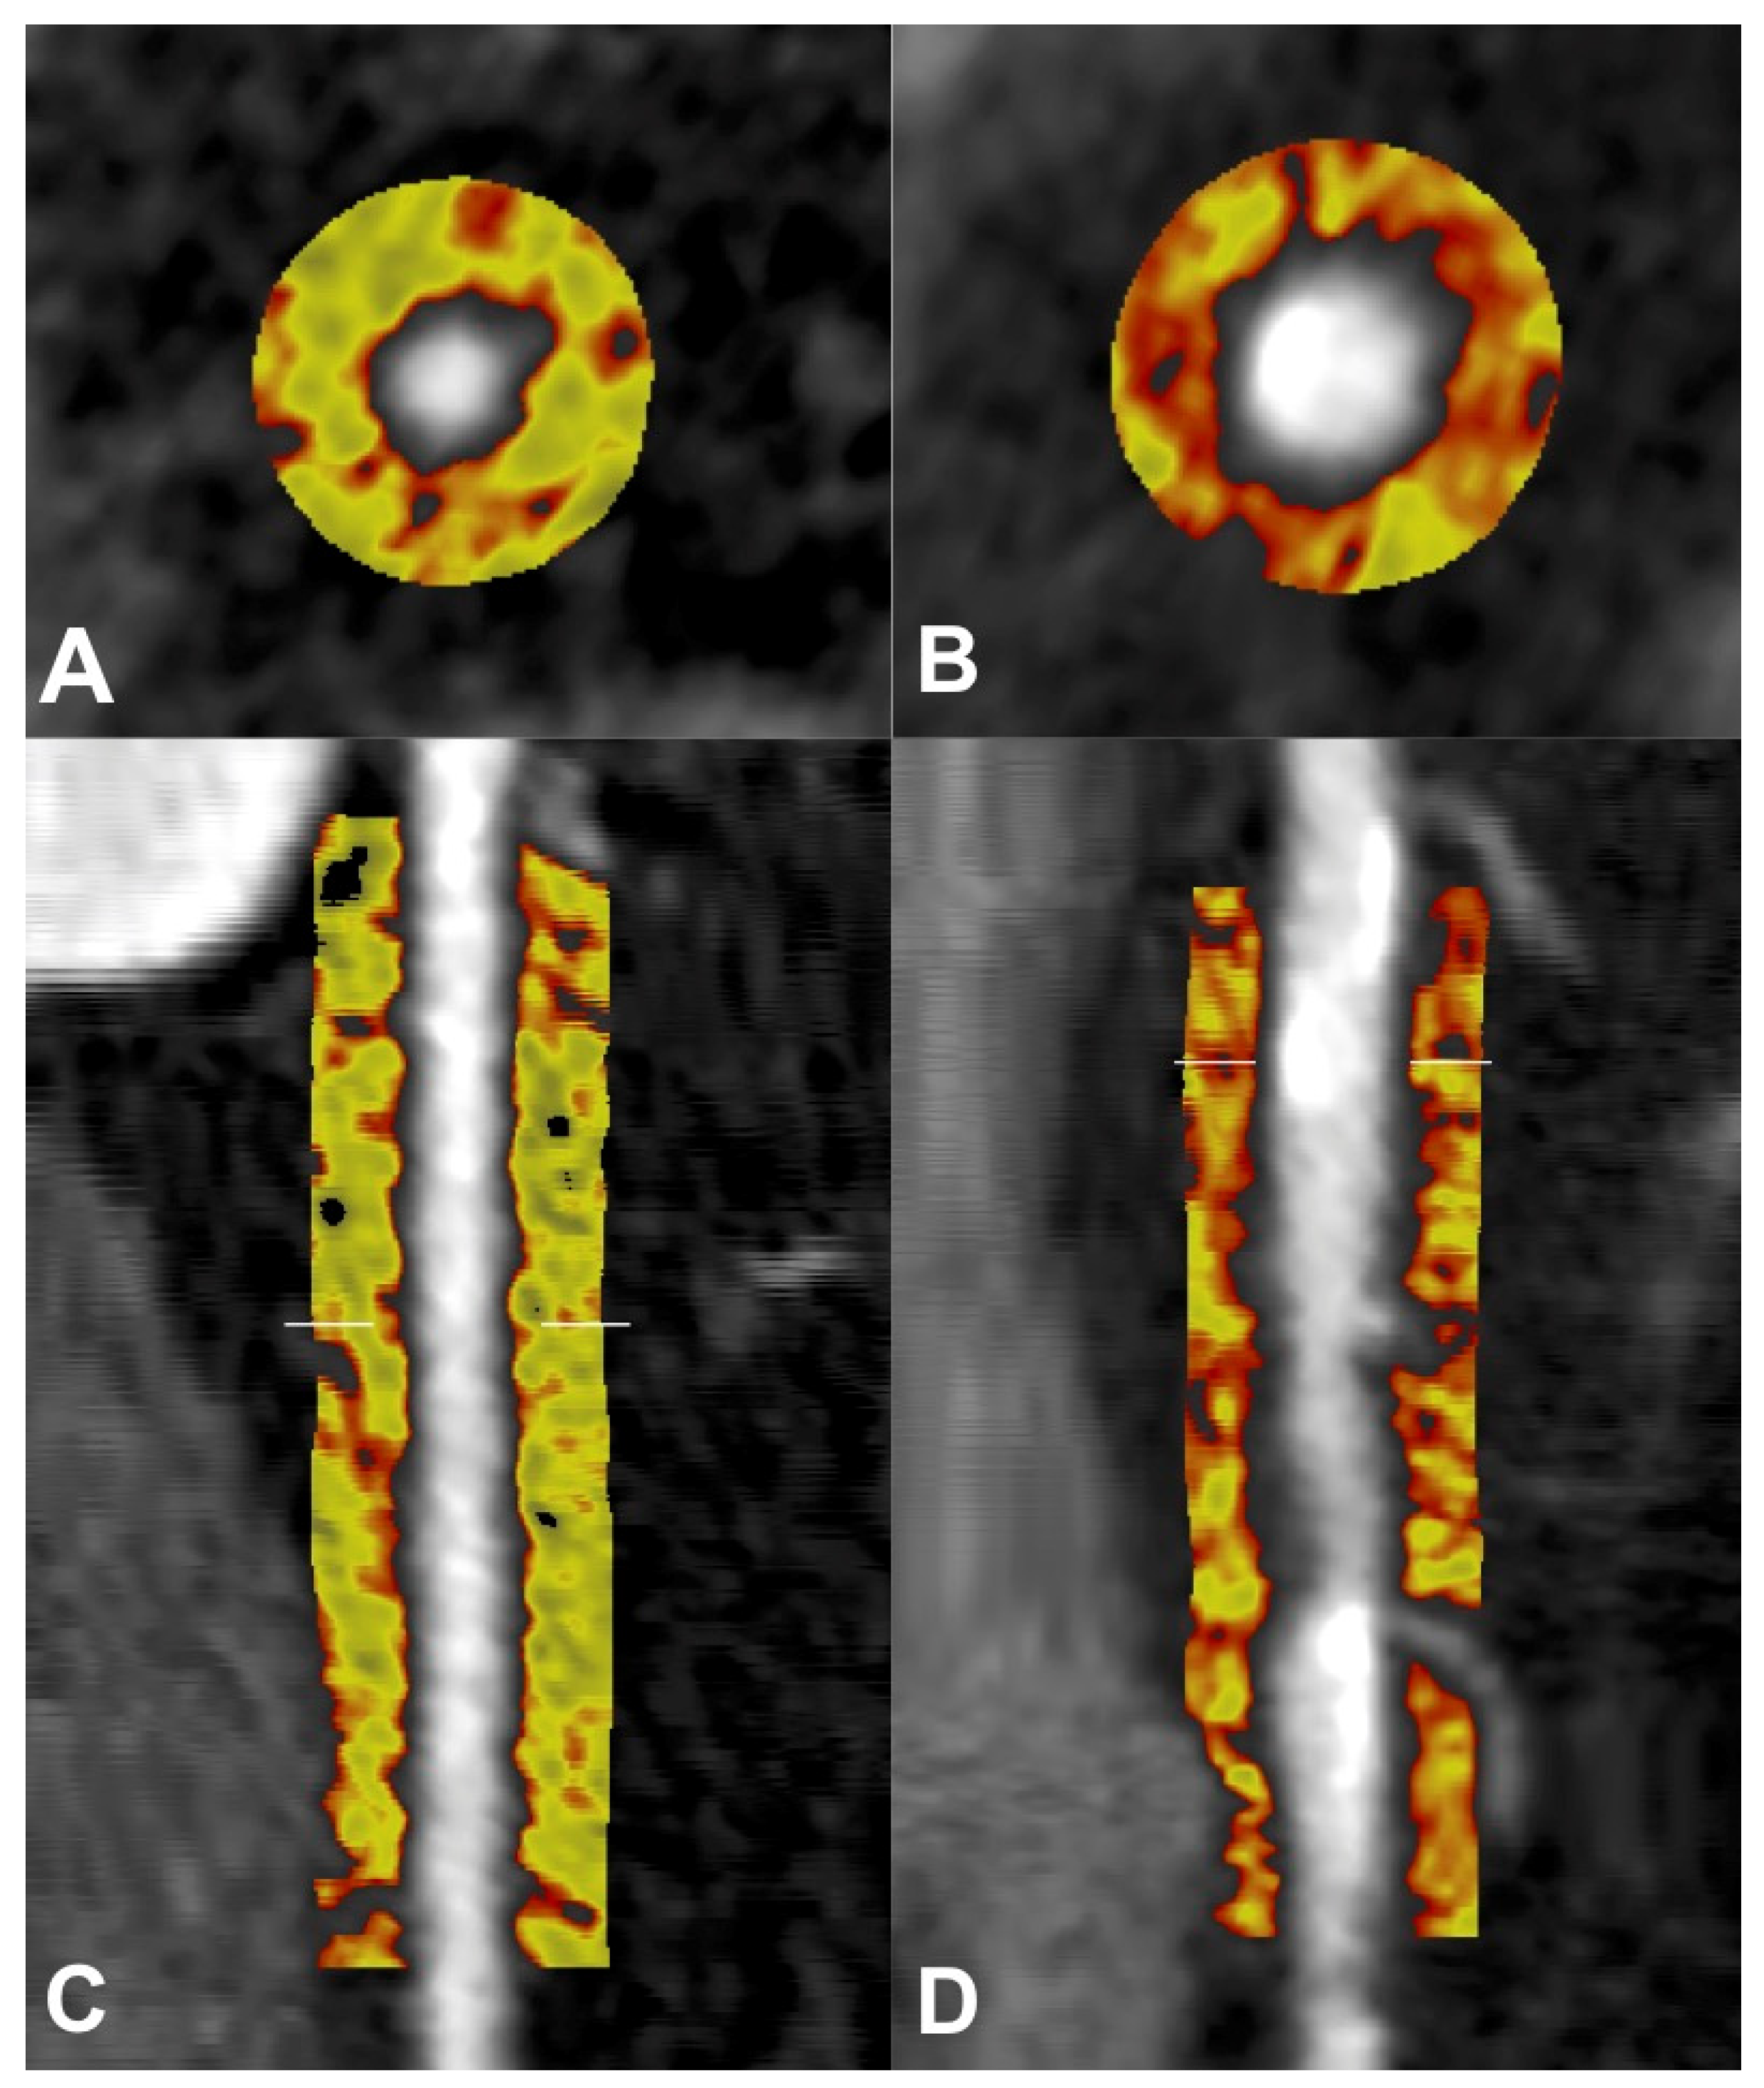

5.2. Pericoronary Fat Attenuation Index

5.3. ‘Crude’ PCAT Attenuation and CAD